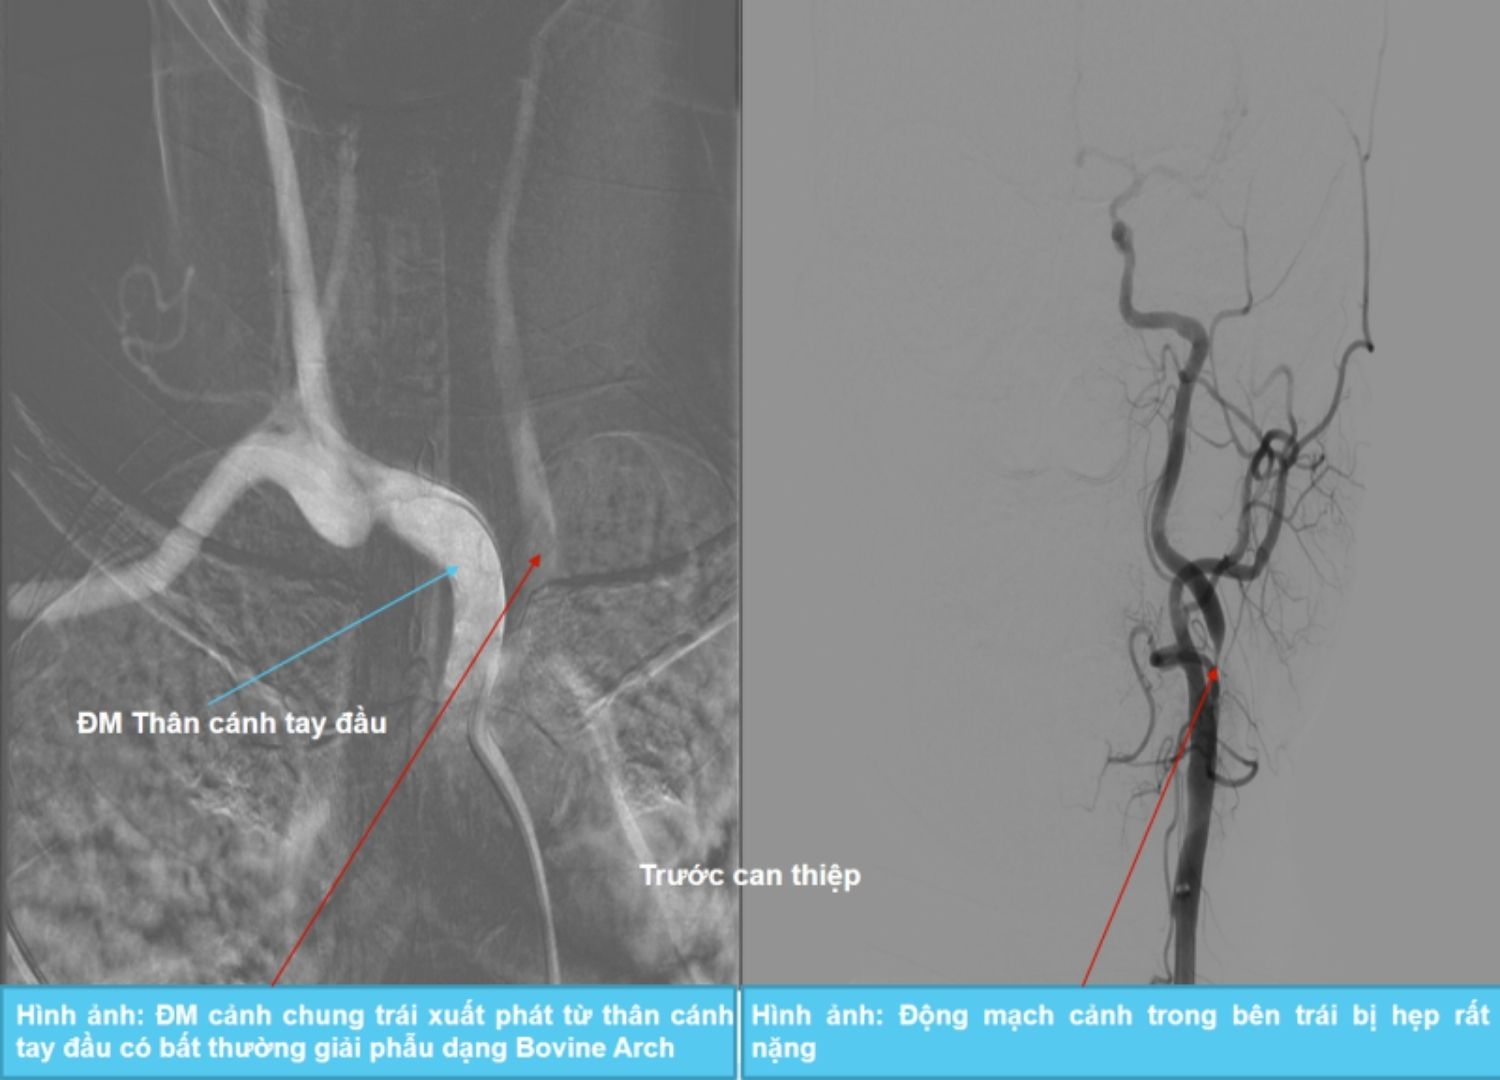

Kết quả chụp cộng hưởng từ sọ não – mạch não cho thấy hình ảnh nhồi máu lồi thể trai, tổn thương thoái hóa myelin chất trắng, kèm hẹp nặng động mạch cảnh trong bên trái và teo nhỏ động mạch cảnh trong bên phải – nguyên nhân chính gây thiếu máu não.

Đặc biệt, bệnh nhân có bất thường giải phẫu dạng Bovine Arch – khi động mạch cảnh chung trái không xuất phát từ cung động mạch chủ như thông thường, mà từ thân động mạch cánh tay đầu. Đây là một bất thường chỉ gặp ở khoảng 15% dân số và làm thay đổi hướng đi của ống thông trong kỹ thuật can thiệp, gây khó khăn cho bác sĩ.

Trước tình trạng này, ThS.BS Giáp Hùng Mạnh cùng ekip đã quyết định can thiệp nong và đặt stent động mạch cảnh trong trái nhằm tái thông dòng chảy lên não cho bệnh nhân. Dưới hướng dẫn của hệ thống chụp mạch số hóa xóa nền DSA, ca can thiệp được thực hiện thành công, giúp mở rộng lòng mạch và phục hồi lưu lượng máu lên não hiệu quả.